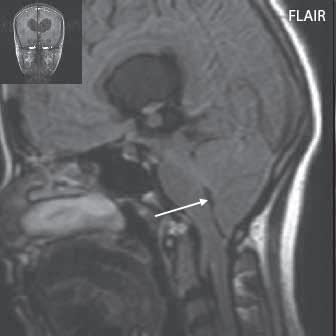

I.1.7 Chiariho malformace (ArnoldovaChiariho malformace)

Rozlišujeme tři formy (typy) této malformace. Chiari I je charakterizován sestoupením mozečkových tonzil do foramen okcipitale magnum do oblasti krční páteře (u dospělých jsou tonzily mozečku max. 5 mm pod úrovní baze lební, u malých dětí (do 10 roků) do 6 mm. Tonzily bývají na podélném řezu přirovnávány ke klínům, které jako by byly zatlučeny do týlního otvoru „pek like“. Chiari II malformace je ve 100 % doprovázena otevřeným spinálním dysrafismem (obvykle myelomeningokélou). Chiari III lze definovat jako Chiari II + okcipitální nebo cervikální encefalomeningokéla. Chiari IV, kde je navíc přítomna hypoplazie mozečku, do této skupiny nezařazujeme, vývojově patří do poruch ventrální indukce.

Chiari II: CT a MR zobrazí malou zadní jámu lební, absenci nebo výraznou redukci cisterny cerebelomedulární a dalších kmenových cisteren, konkávní klivus. Mohou být abnormality v oblasti foramen okcipitale magnum, nízký úpon tentoria, někdy absence nebo fenestrace falx cerebri. MR lépe ukáže kaudálně uloženou a protáhlou IV. komoru (někdy je přirovnávána až ke stéblu slámy), protažený pons a další možné, přidružené abnormality (hydrosyringomyelii, agenezi, hypogenezi nebo fenestraci corpus callosum…).

U Chiari II malformace je klinický obraz ovlivněn myelomeningokélou, bývá přítomna paraparéza DK, poruchy sfinkterů, při dekompenzaci hydrocefalu, se mohou objevit kmenové příznaky. Léčbou je řešení spinálního dysrafismu, hydrocefalu (obnova normální cirkulace likvoru), dekomprese v subokcipitální oblasti.

Obr. I.1.7b Sestup mozečkových tonzil, „pek like“ (šipka), Chiariho malformace I c d

Sestup mozečkových tonzil,

Myelomeningokéla

Obr. I.1.7e Myelomeningokéla již po operačním překrytí kožním krytem, Chiari II; stejný pacient jako na obr I 1 7c, d

Obr. I.1.7f Myelomeningokéla již po operačním překrytí kožním krytem, míšní nervy probíhají směrem ventrálním od nervové plakody (šipka), Chiari II; stejný pacient jako na obr I 1 7c, d, e